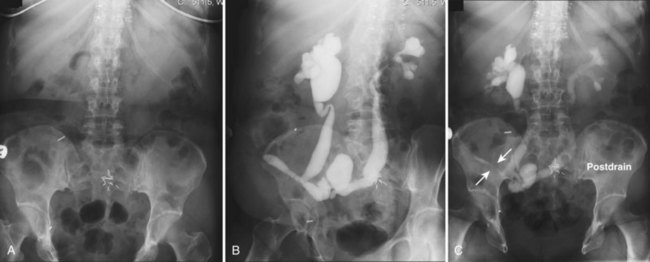

The patient is positioned supine. An abdominal plain radiograph is obtained before the introduction of contrast material (Fig. 4–8A). A commonly employed technique is to insert a small-gauge catheter into the ostomy of the loop, advancing it just proximal to the abdominal wall fascia. The balloon on such a catheter can then be inflated to 5 to 10 mL with sterile water. By gently introducing contrast through the catheter, the loop can be distended, usually producing bilateral reflux into the upper tracts. Oblique films should be obtained in order to evaluate the entire length of the loop (Fig. 4–8B). Because of the angle at which many loops are constructed, a traditional anteroposterior (AP) view will often show a foreshortened loop and could miss a substantial pathology. A drain film should be obtained (Fig. 4–8C). This may demonstrate whether there is obstruction of the conduit.

Figure 4–8 Loopography in a patient with epispadias/exstrophy and ileal conduit urinary diversion. The plain film (A) shows wide diastasis of the pubic symphysis. After contrast administration via a catheter placed in the ileal conduit, free reflux of both ureterointestinal anastomoses is demonstrated (B). A postdrain radiograph (C) demonstrates persistent dilation of the proximal loop indicating mechanical obstruction of the conduit (arrows).